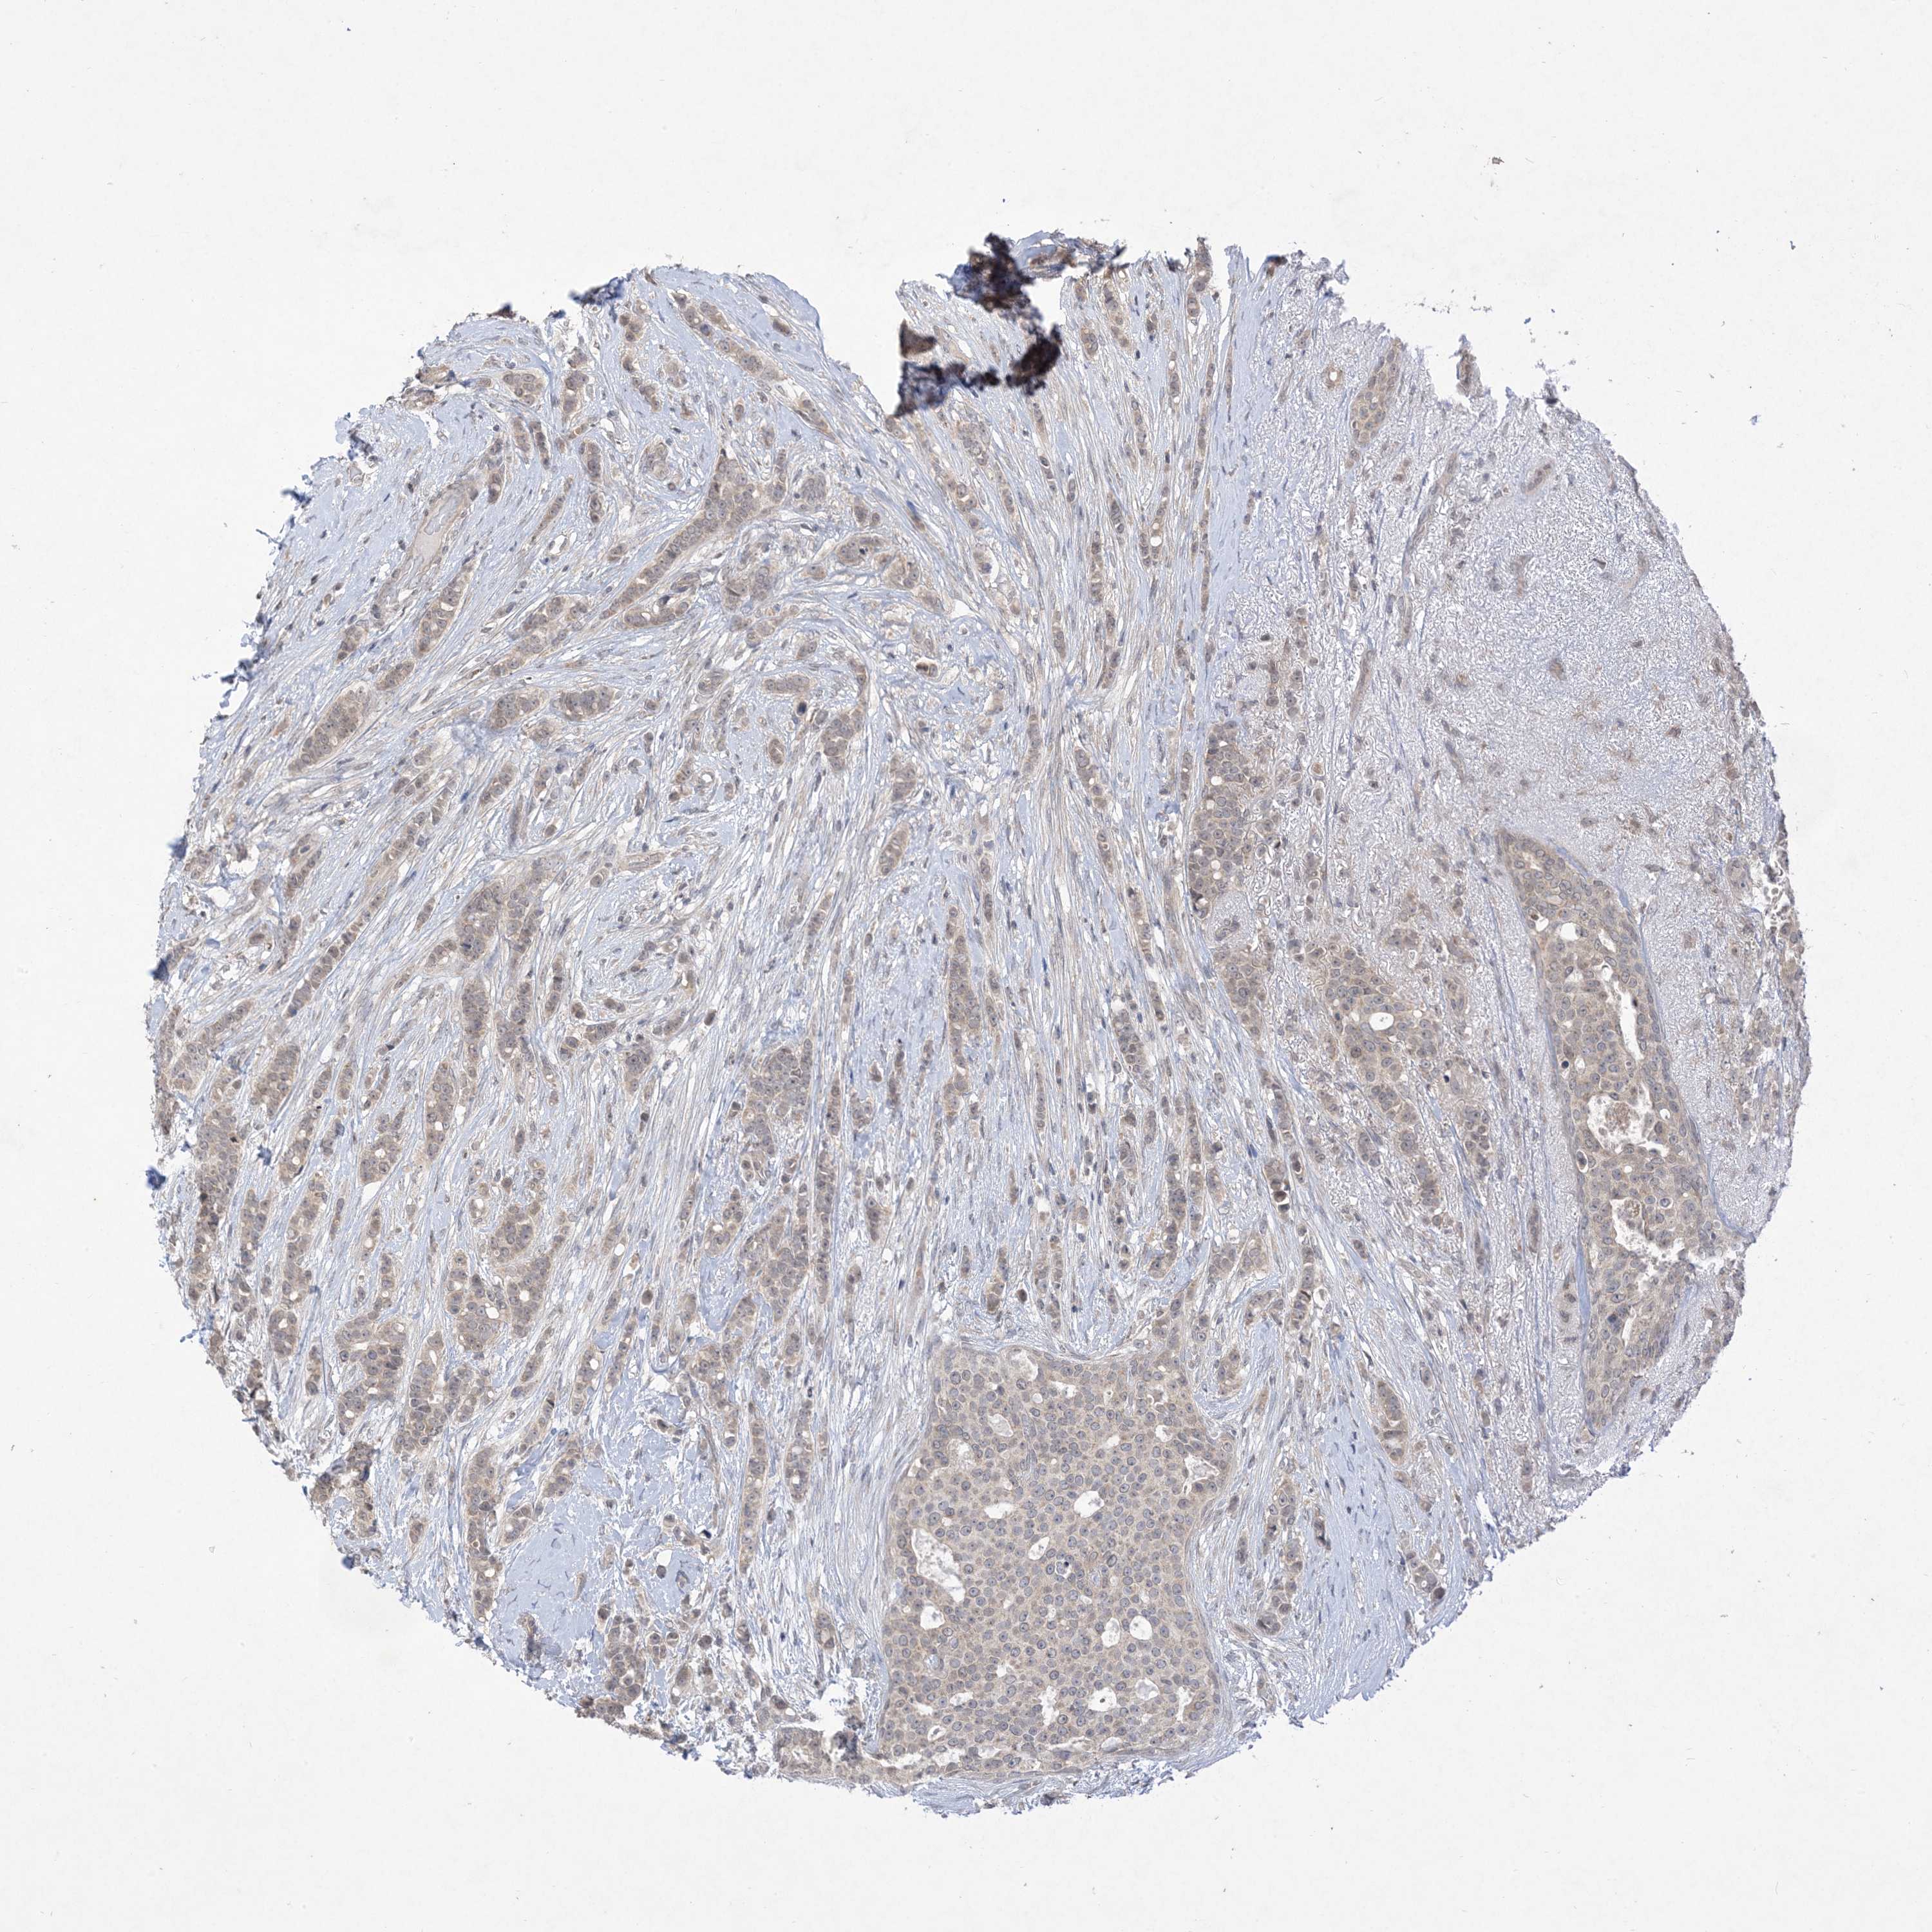

BRCA TCGA BRCA VALIDATION PROTEIN EXPRESSION